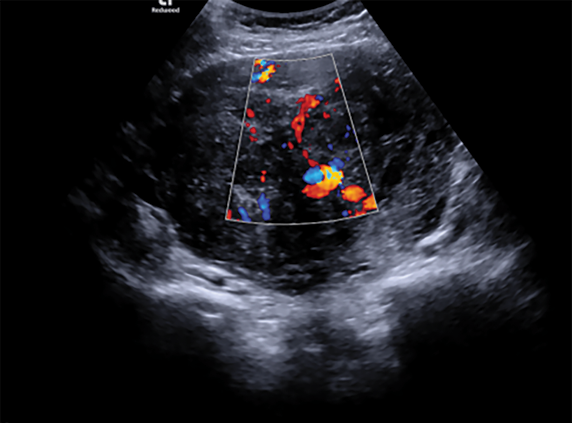

Atlikus ginekologinę apžiūrą nustatyta, kad gimda palpuojant padidėjusi ir nelygi, gimdos priedai atskirai neišpalpuoti. Transvaginalinio ultragarsinio tyrimo metu gimdos kūno projekcijoje rastas didelių matmenų mišrios echostruktūros darinys, turintis kraujotaką. Darinio dydis ‒ 9,84×11,38 cm. Gimda ir kiaušidės atskirai nevizualizuotos, laisvo skysčio ar papildomų darinių mažajame dubenyje nenustatyta (1 ir 2 pav.).

2 pav. Gimdos darinio kraujotakos vizualizacija, pritaikius spalvinę doplerografiją